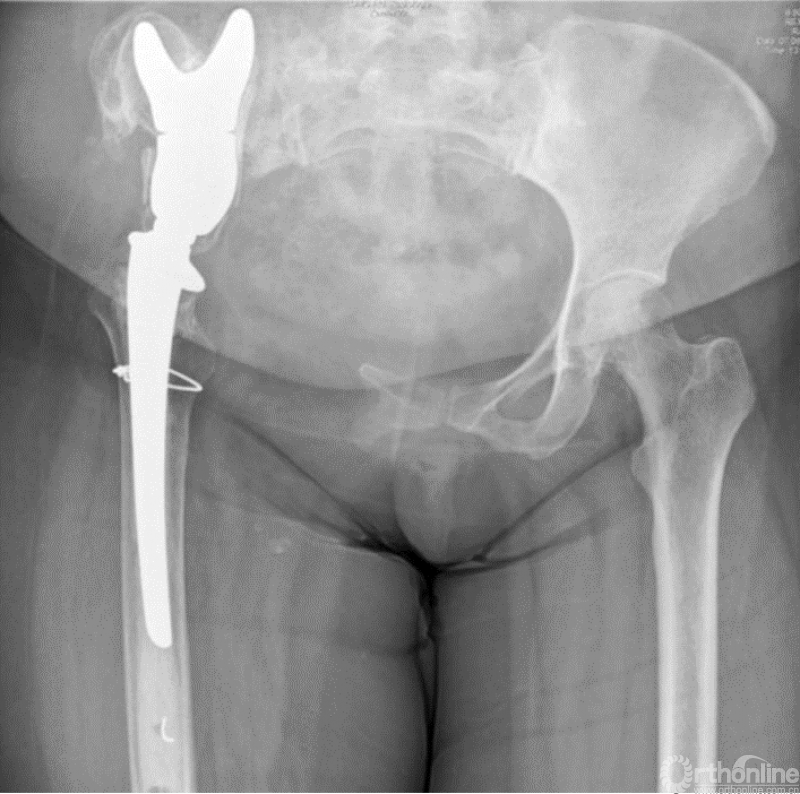

马鞍式假体未与宿主骨形成稳定的骨性连接,整体功能较差,并且并发症发生率较高[2-5](图1)。冰激凌假体与宿主骨的连接更加紧密,但不适合骨盆I区大部分切除的骨缺损,不能重建完整骨盆环[6-10](图2)。组配式半骨盆假体组装灵活,且可进行骨盆环完整重建,但其安装技术要求高,假体组件间存在断裂风险,不匹配得假体与宿主骨锚定将直接影响骨整合,最终易导致松动[1,11-15](图3)。

图2 冰激凌假体